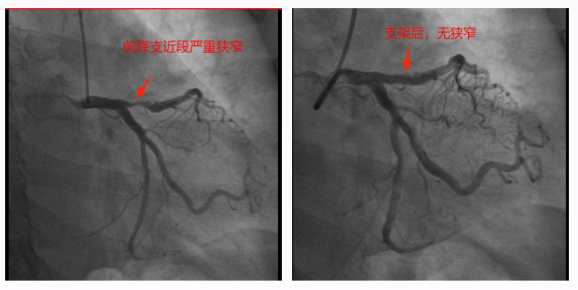

锦旗赠送人:王阿姨及家人。 受表扬者:心血管内科二区刘富湘及全体医护人员。 近日,我院心血管内科二区收到一份特殊的感谢——刚顺利康复出院的王阿姨,将一面印着“医术精湛 务实笃行 真诚敬业 仁心仁德”的锦旗送到医护人员手中,以此表达对医护团队诊疗与照护的认可。 今年60岁的王阿姨有高血压、糖尿病病史,此前因心悸胸闷不适7天入院,症状呈阵发性发作,还伴有压榨感。心电图提示ST改变,结合其基础疾病与症状特点,心血管内科二区主任刘富湘及主管医师罗向卫判断,王阿姨可能患有不稳定型心绞痛,存在进展为心肌梗死的风险。 为进一步明确病情,医护团队迅速为其安排冠脉造影术,结果显示:王阿姨右冠狭窄85%-95%,远端侧枝供血前降支远端;前降支近段硬化伴狭窄90%;回旋支远端狭窄30%。考虑到王阿姨患有糖尿病,若一次手术处理两条血管,不仅手术时间长、单次造影剂用量大,还可能损伤肾功能,且手术风险会显著增高。经过仔细考量,团队最终制定分次手术方案,优先处理狭窄最严重的右冠,并植入一枚支架。 ▲右冠近段支架前后 ▲前降支近段支架前后 一个月后,王阿姨恢复良好,团队再次为其完成前降支手术。术后,王阿姨两支冠脉恢复充足血流,未出现心肌梗死、心衰等不良后果,肾功能也无明显损害,心悸胸闷症状明显缓解,顺利康复出院。 从入院时的焦虑不适,到出院时的轻松安心,王阿姨的好转离不开心内二区医护人员的专业诊疗与悉心照护。这面锦旗,是患者对团队技术与服务的肯定,更是团队继续守护百姓心脏健康的动力。